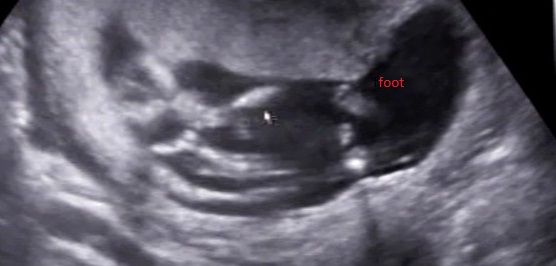

Could the thing between the feet in the second pic be boy parts or its too big to be that?

There also look like boy parts in the last pic if it's a potty shot?

Thanks =) Yes the last is a potty shot:) She explained that she saw three dots in a triangle, but I didnt really see them haha.

I would be pleased with the 3rd shot...and yes, that little spare part can look a lot bigger than you think it can at that stage.